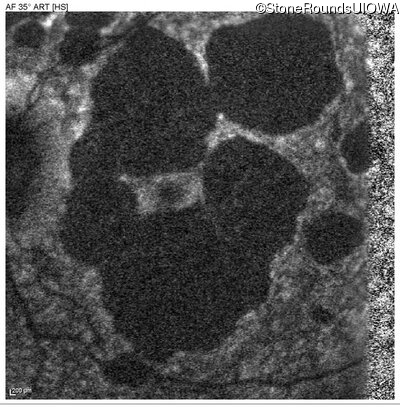

Blue Autofluorescence - Right - 20/40 -2

Exemplar